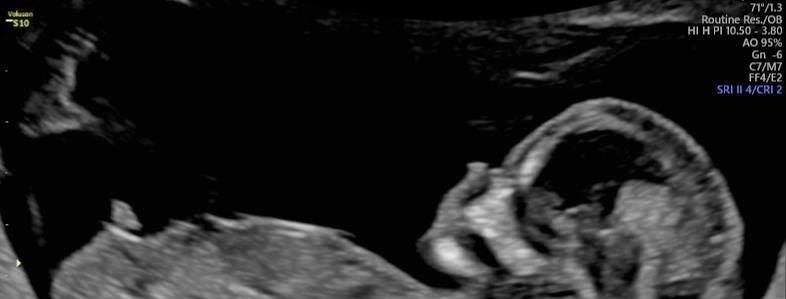

Je wordt opgeleid om zelfstandig 1e trimester en 2e/3e trimester echo’s uit te voeren. Na afloop van de opleiding kan je:

• vitaliteit beoordelen en graviditeit lokaliseren

• een meerlingzwangerschap vaststellen of uitsluiten, inclusief chorioniciteit

• termijn bepalen; CRL meten

• biometrie (DBP, HC, TCD, AC, FL) uitvoeren

• ligging foetus en placenta bepalen

• vruchtwater meten